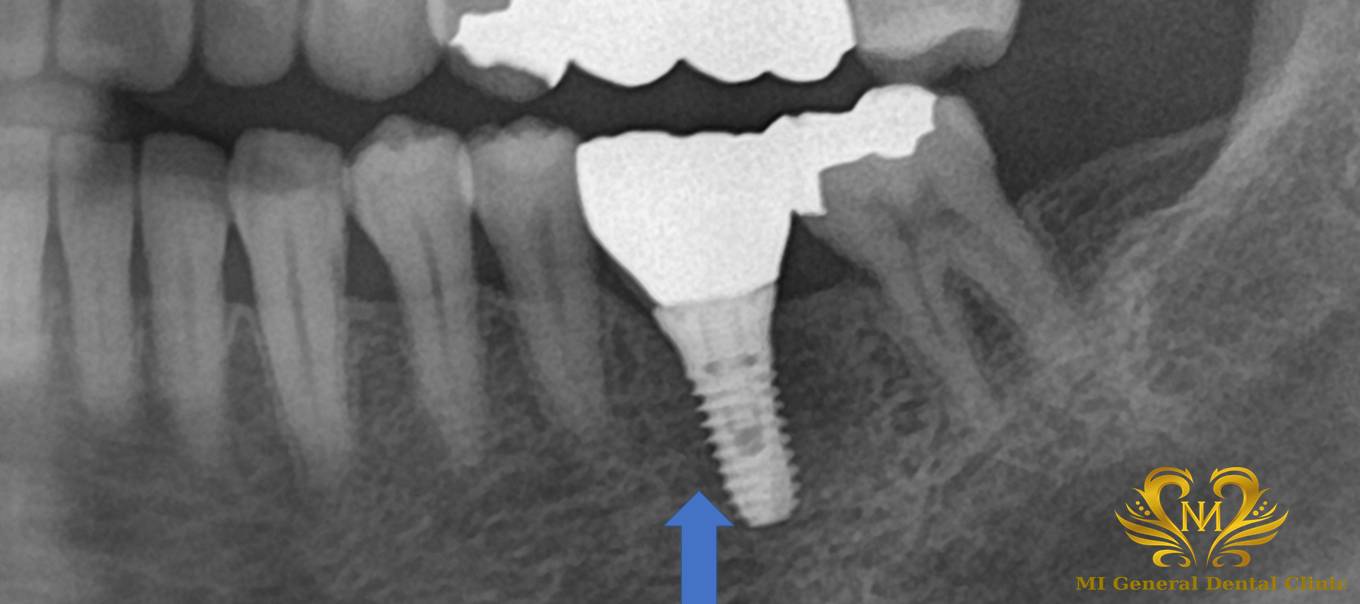

治療後

患者様はインプラント治療を選択され、インプラント手術を行いました。

今回の手術後は、インプラントが顎の骨としっかり結合するまで約3か月間待ちます。

3か月後に、インプラントが骨にしっかり固定されていることを確認したうえで、被せ物の型取りを行いました。

その後、完成した被せ物を装着し、しっかり噛める状態に回復しました。

今回のケースでは、初診から約5か月で最終的な被せ物まで治療が完了しました。